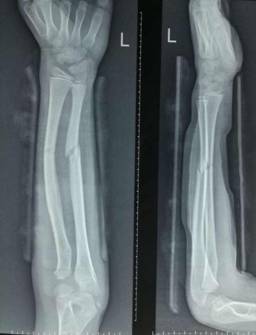

手法复位小夹板固定治疗骨折

优点:免于开刀之苦。

西医手术先进全面:运用DCO理念,阶梯序贯抢救及治疗严重骨盆骨折、多发性、开放性重大骨折创伤;常规开展复杂骨盆髋臼骨折、手足显微外科的手术治疗;以最先进的生物学固定理念为指导,运用微创手术技术治疗骨折,包括:四肢长骨骨折的交锁髓内固定技术、MIPPO(微创经皮钢板内固定技术)、股骨近端骨折髓内固定技术(PFNA)、外固定支架固定技术等等均达国内先进水平。

微创治疗肱骨干骨折

优点:闭合复位,不干扰骨折断端,中心固定,利于愈合。